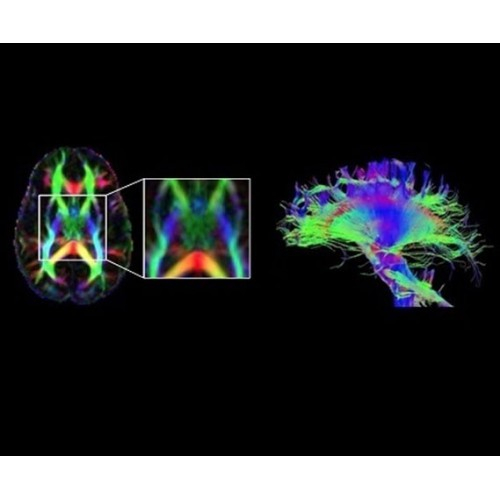

В систему SIGNA PET/MR встроены запатентованные детекторы кремниевого фотоумножителя (SiPM) и сверхчувствительные кристаллические сцинтилляторы на основе лютеция толщиной 25 мм. Благодаря этому обеспечивается исключительная чувствительность и возможность использования времяпролетной диагностики (TOF).

Кроме того, в результате использования технологии TOF и инновационной технологии реконструкции Q.Clear вы сможете добиться прекрасного соотношения сигнал/шум. А благодаря технологии нулевого времени эхо (ZTE) визуализировать костную структуру без ионизирующего излучения. Все эти разработки для улучшения качества сканирования и точности анализа помогут вам использовать весь потенциал ПЭТ/МРТ.

В системе SIGNA PET/MR есть все инструменты, необходимые для выявления маркеров разных заболеваний и для создания новых протоколов. ПЭТ/МРТ можно использовать совместно с мультиядерной спектроскопией в лаборатории in vivo для изучения быстрых биохимических процессов. Кроме того, PET ToolBox и набор инструментов Orchestra предоставляют персональный доступ к функциям реконструкции изображений для ПЭТ и МРТ, ускоряя и упрощая работу с необработанными данными.

• Orchestra — получайте прямой доступ к необработанным данным изображений для редактирования в среде реконструкции с SIGNA PET/MR.

• PET ToolBox — разрабатывайте новые методики ПЭТ с помощью наших программных инструментов для доступа к среде реконструкции ПЭТ-изображений.

• In vivo лаборатория — получайте полные данные биохимических процессов in vivo с мультиядерной спектроскопией на SIGNA PET/MR.